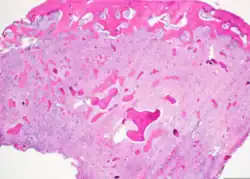

Cemento-ossifying fibroma is a well-demarcated lesion, often encapsulated by a thin fibrous capsule and sharply separated from adjacent normal bone. It shows significant internal variation, with differing amounts of fibrous and mineralized tissue—even within the same lesion. Mineralization is often more prominent centrally and typically includes osteoid, woven to lamellar bone, and dense basophilic cementum-like calcifications. Bony trabeculae may fuse into broad sheets or form thick, anastomosing strands. Osteoblastic rimming is commonly seen around bone trabeculae.[27]

The stroma is fibroblastic and may exhibit areas of hypercellularity and nuclear hyperchromasia; however, mitotic activity is rare and cellular atypia is minimal .[28] The mineralized component may include acellular or paucicellular cementum-like spheres along with bone structures .[28]

Though rare, hemorrhagic cystic degeneration—resembling aneurysmal bone cyst formation—can occur, more commonly in juvenile variants.[27][29] Histological overlap can exist among subtypes: psammomatoid and trabecular JOF may exhibit features resembling COF, and vice versa. In syndromic cases, such as gnathodiaphyseal dysplasia, COF lesions appear more fibrous with basophilic, acellular bone droplets and spherical ossicles, but histologically resemble nonsyndromic counterparts .[30]